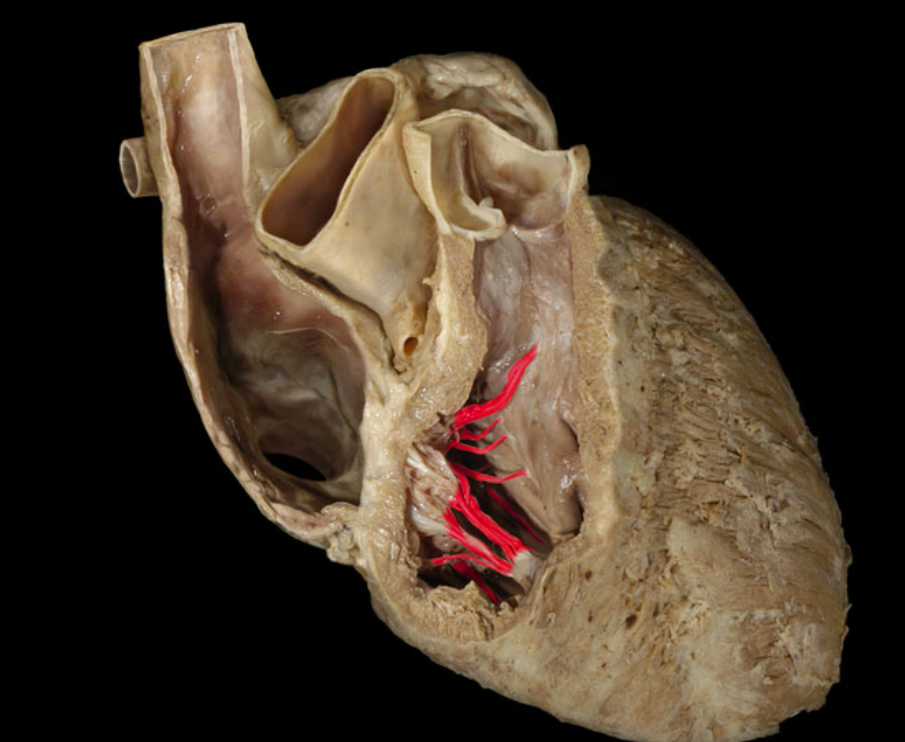

The tricuspid valve is located

between the right atrium and right ventricle

Closing of the tricuspid valve

How does the tricuspid valve close?

The contraction of the right ventricle forces blood against the cusps, which closes the valve.

Which valve is found between the right ventricle and the pulmonary trunk?

The pulmonary valve

What chamber of the heart pumps blood into the pulmonary trunk?

The right ventricle

Blood from the right ventricle flows to the_____ ______which then splits into two arteries (left and right) that lead into the lungs.

pulmonary, trunk

Chordae tendineae

Right atrioventricular valve